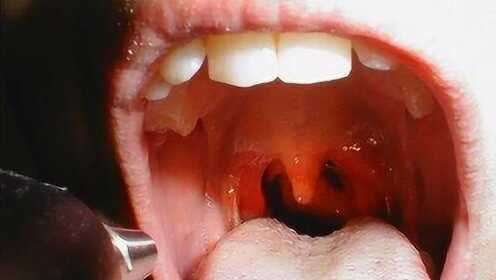

慢性咽炎是一種常見的喉部疾病,主要表現為咽部不適、干燥、瘙癢、疼痛等癥狀,由于長期受到刺激或感染,咽部黏膜出現慢性炎癥表現,慢性咽炎雖然不是嚴重疾病,但癥狀反復發(fā)作,嚴重影響患者的生活質量。